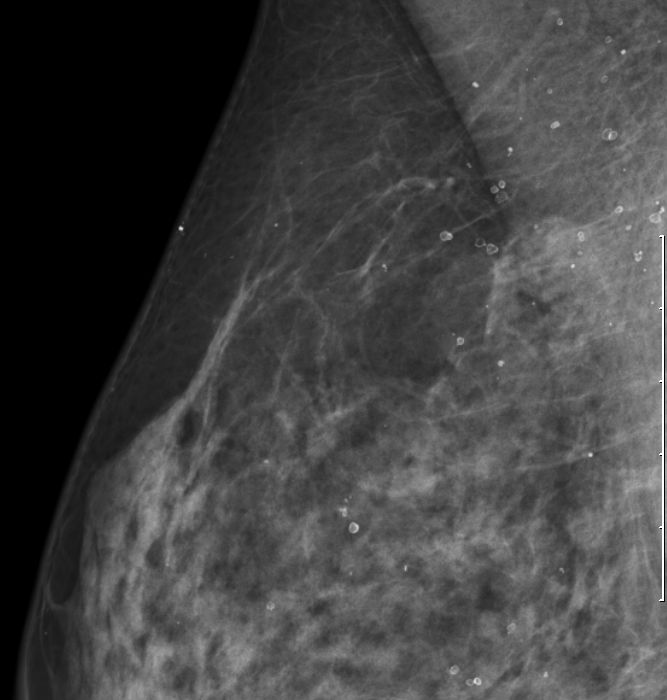

| Verkalkungen | Blunt duct adenosis. Schalenförmige

Verkalkungen im Milimeterbereich. Immer gutartig.